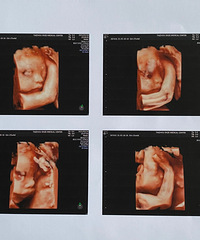

预产期:2022.08.30建卡医院:台州妇女儿童医院产检医院:台州妇女儿童医院胎宝宝小名:未定生产医院:台州妇女儿童医院B超照片/孕期相关照片一张:

预产期:2022年4月10日建卡医院:椒江妇幼保健所产检医院:椒江妇幼保健所胎宝宝小名:崽生产医院:台州妇女儿童医院或路桥恩泽医院B超照片/孕期相关照

预产期:2022/2/20建卡医院:路桥路北卫生院产检医院:椒江妇幼保健所胎宝宝小名:肉肉生产医院:考虑妇女儿童医院,台州市中心医院,第一张B超照片:

预产期:2021.11.8建卡医院:台州妇女儿童医院产检医院:台州妇女儿童医院胎宝宝小名:未起生产医院:台州妇女儿童医院B超照片/孕期相关照片一张:

预产期:2021.2.13建卡医院:台州医院产检医院:台州医院胎宝宝小名:由由/小丸子/绵绵/boly生产医院:看情况吧B超照片/孕期相关照片一张:

预产期:2021年4月19日(提前3月10日生)建卡医院:桐屿卫生院产检医院:恩泽宝宝小名:牛小壮生产医院:恩泽B超照片/孕期相关照片一张:

预产期:2022.2.4建卡医院:临海邵家渡卫生院产检医院:恩泽妇产+临海妇幼保健院胎宝宝小名:lucky生产医院:预计台州医院新院B超照片/孕期相关照片一